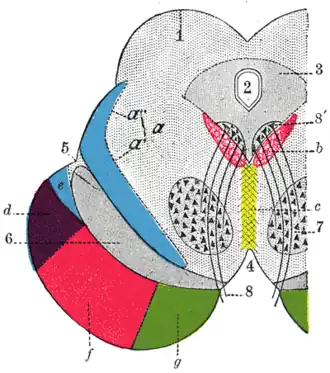

Вокруг водопровода располагается центральное серое вещество, в котором заложены ретикулярная формация, ядра III и ядра IV пар черепных нервов и др. На сечениях среднего мозга сильвиев водопровод может иметь вид треугольника, ромба или эллипса. Через него происходит циркуляция ликвора (спинномозговой жидкости)[1][2].

У человека представляет собой канал длиной около 15 мм, соединяющий в головном мозгу полость третьего желудочка головного мозга с четвертым[1]. Дорсальную стенку образует пластинка четверохолмия среднего мозга, вентральную — покрышка ножек мозга. Образуется в онтогенезе из полости третьего мозгового пузыря[2].

Вокруг Сильвиева водопровода находится центральное серое вещество (substantia grisea centralis)[2], анатомически относящееся к покрышке среднего мозга. Это серое вещество направляет свои восходящие проекции в ядра шва и в голубое пятно, а также в соматосенсорные и висцеросенсорные ядра таламуса. Оно также имеет нисходящие проекции в спинной мозг. Восходящие нервные волокна спиноталамического пути, проводящие ощущения боли и температуры, на своём пути в таламус делают промежуточную «остановку» в околоводопроводном сером веществе. Эта часть спиноталамического пути называется спиномезэнцефалическим путём. В свою очередь, воспринимающие болевые и температурные ощущения ядра таламуса направляют свои нисходящие волокна обратной связи к спинному мозгу также через центральное серое вещество. В центральном сером веществе в области дна водопровода располагаются ядра двух пар черепных нервов. на уровне верхних холмиков четверохолмия среднего мозга, ближе к срединной линии залегает парное ядро глазодвигательного нерва (III пара черепных нервов). Вентральнее от него залегает добавочное ядро глазодвигательного нерва (n. oculomotorius accessorius) — ядро Якубовича (Ядро Эдингера-Вестфаля). Несколько выше и кпереди от ядра глазодвигательного нерва залегает одно из ядер ретикулярной формации — промежуточное ядро (nucleus interstitialis, ядро Кахаля)[2].

Поперечный разрез среднего мозга. Цифрой 2 показан водопровод мозга

Поперечный разрез среднего мозга. Цифрой 2 показан водопровод мозга Поперечный разрез среднего мозга на уровне нижнего двухолмия.